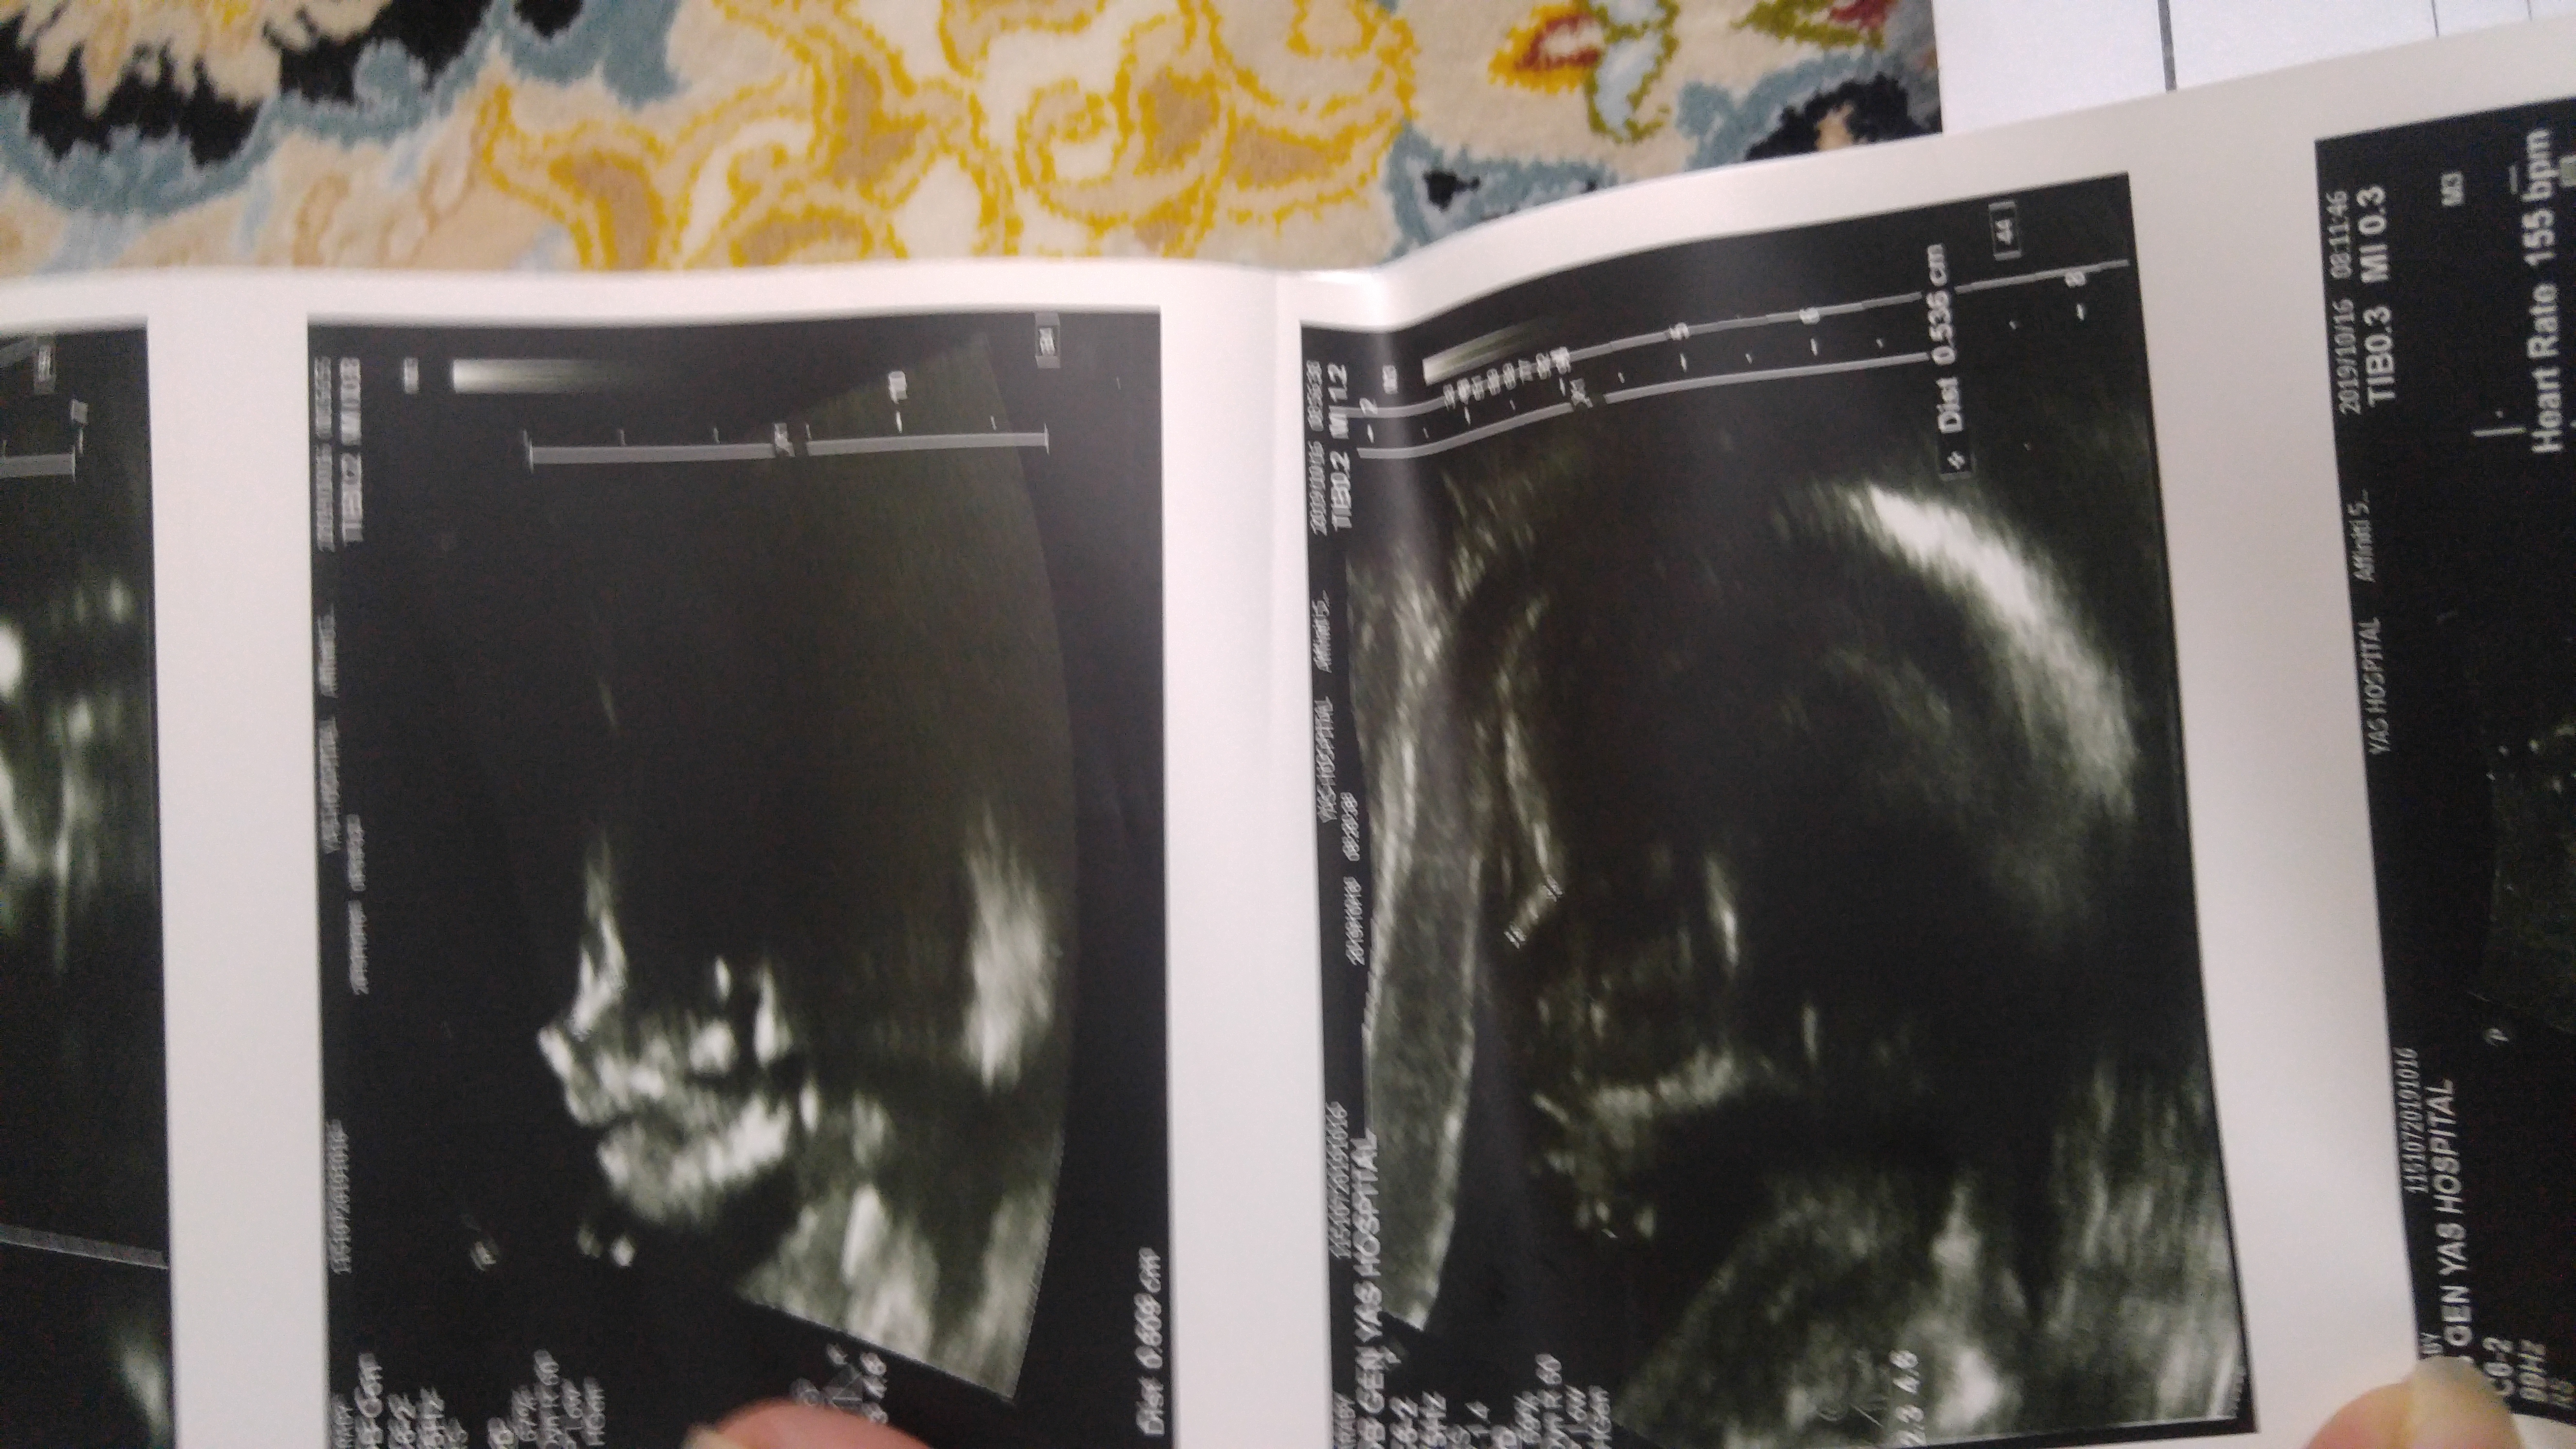

هفته 20 ...4 روز پیش رفتم سونو

نه اصلا عکس واضح ندارم ازش....چندتا دادن نمیدونم چی به چیه

اینابودن نمیدونم اوکی هست یا نه